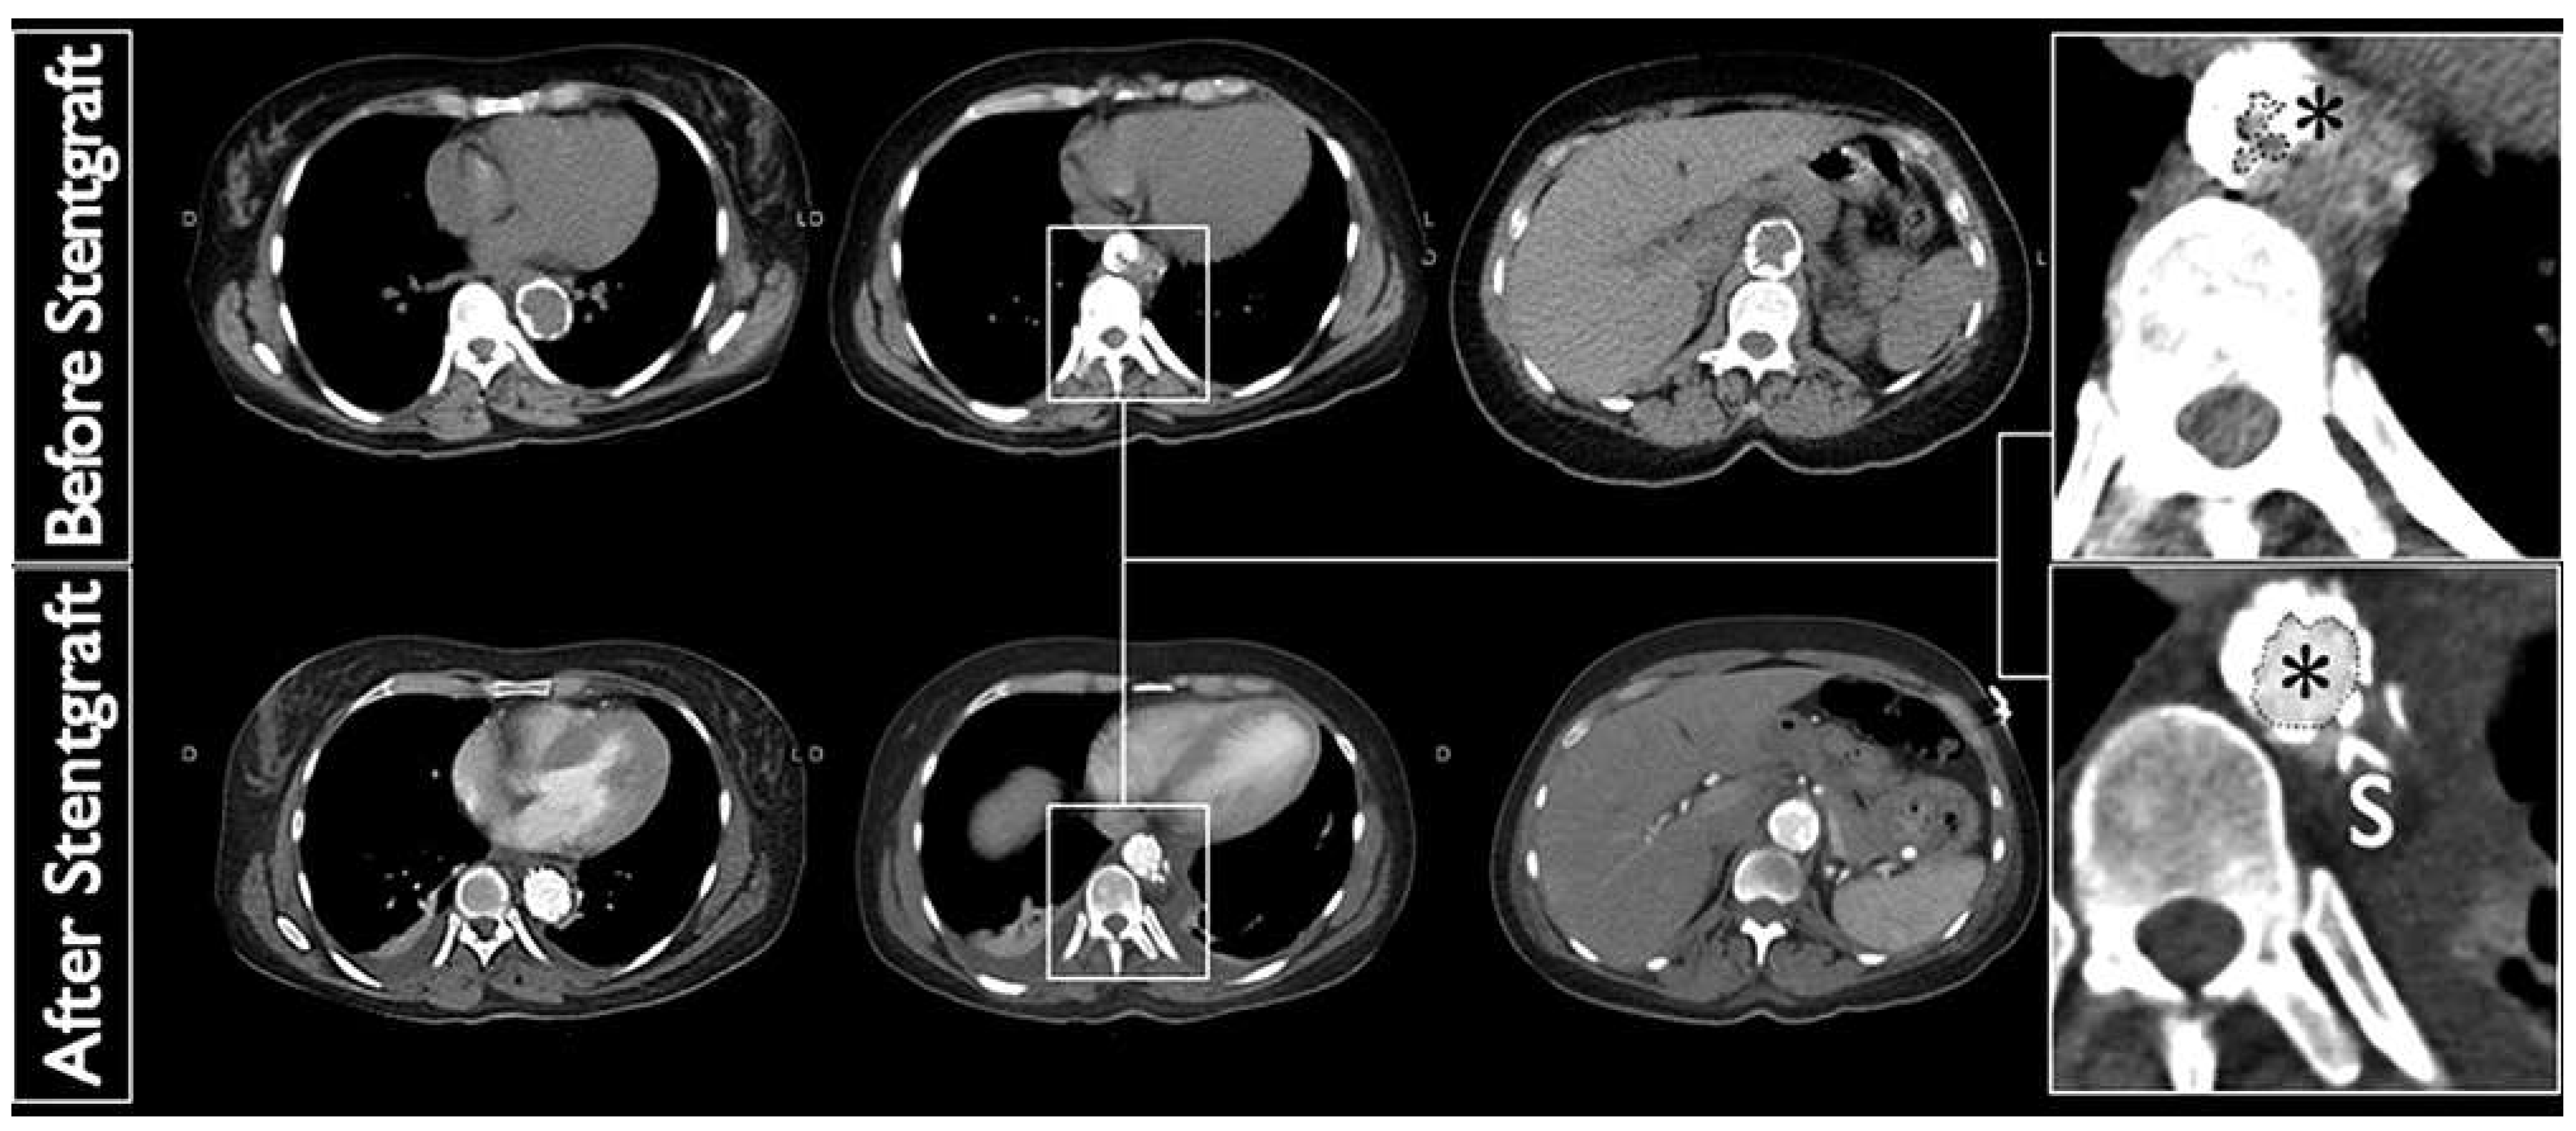

Figure 2. Computed tomography angiography of the thoracic aorta before (top) and after (bottom) endovascular stent-graft (26/100 mm-Valiant Captivia Thoracic-Medtronic) implantation with significant acute luminal gain (*).

The location of the kinking and maximal lumen reduction were considered suitable for an endovascular approach. The patient underwent a transfemoral endovascular stent graft placement with a 26/100 mm Valiant Captivia Thoracic stent graft (Medtronic). The postinterventional angiographic assessment was satis factory (Figure 2). Immediate clinical follow up was unremarkable, with blood pressure in the normal range under treatment with five antihypertensive drugs, and instant relief of the abdominal symptoms.